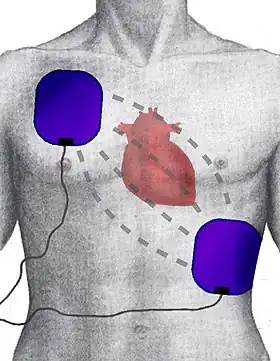

View of defibrillator electrode position and placement | |

Placement

Resuscitation electrodes are placed according to one of two schemes. The anterior-posterior scheme is the preferred scheme for long-term electrode placement. One electrode is placed over the left precordium (the lower part of the chest, in front of the heart). The other electrode is placed on the back, behind the heart in the region between the scapula. This placement is preferred because it is best for non-invasive pacing.

The anterior-apex scheme (anterior-lateral position) can be used when the anterior-posterior scheme is inconvenient or unnecessary. In this scheme, the anterior electrode is placed on the right, below the clavicle. The apex electrode is applied to the left side of the patient, just below and to the left of the pectoral muscle. This scheme works well for defibrillation and cardioversion, as well as for monitoring an ECG.